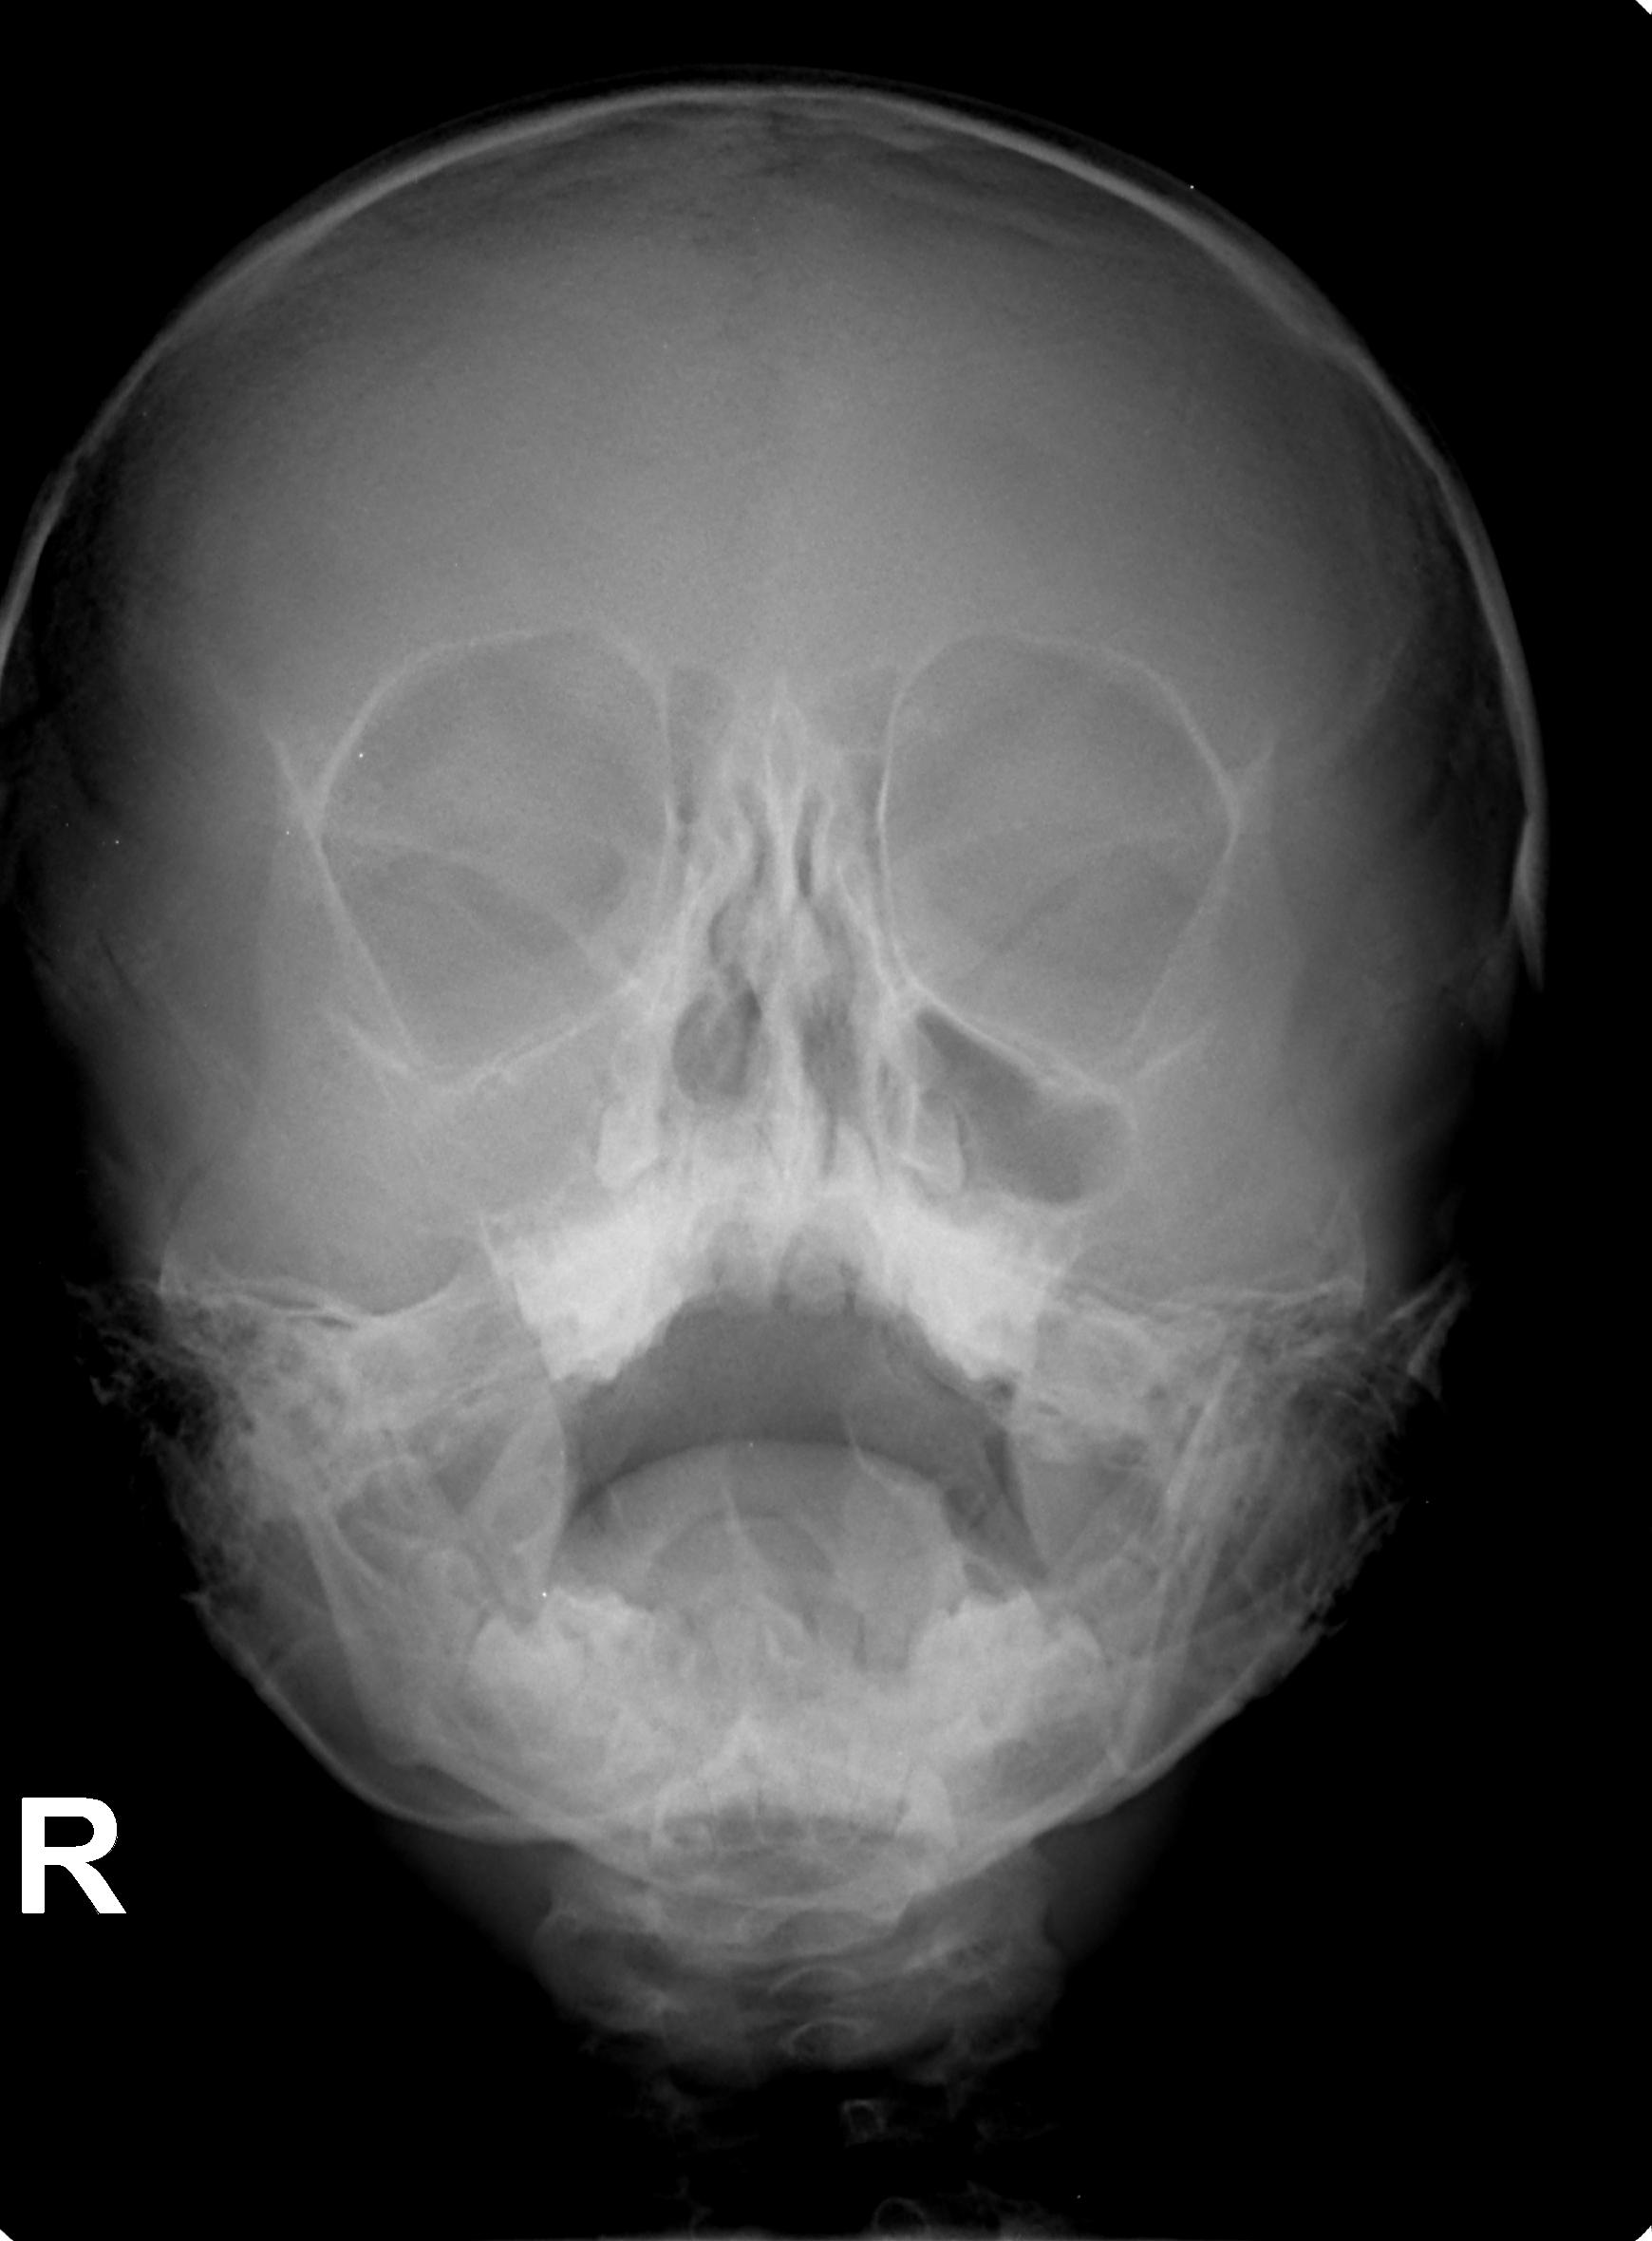

Здравейте имам момче на 5 години, което боледува много и често. Като по малък правеше много често разстройства с вискока температура, което премина след третата година, след това От всяка хрема става усложнение бронхит, пневмония и синузит, с много продължителна и мъчителана кашлица, въпреки че веднага ходим на лекар.Калицата в повечето случай е влажна и отделя храчки с продължителност около 3 седмици, след оздравяването не остава кашлица която да продължи. В всички боледувания се назначава антибиотик минимум за 10 дни и инхалаций с пулмикорт и вентолин.На база ПКк с завишени левкоцити и след лечението ПКК в норма.Като няколко пъти се наблюдава след спиране на пулмикорт , кашлицата се засилва. От няколко специалиста в областа, категорично беше отхвърлено да има данни за муковизцидоза.Наскоро е правно изследване за клостридиум токсин А и Б (-) отрицателен и панкреатитна еластаза в норма. Детето е на 5 години и 3 месеца, висок е 116 см и тежи 26 килограма. Водила съм го на три специалиста уши, нос и гърло. Няма данни за уголемена трета сливица, но има изкривена носна преграда. Преди време бяха изолирани стафилокои и стрептококи пневмоние ( силно резистентна).Като на антибиграма излиза антибиотик който го няма за неговота възраст. Който в последствие уж са изчистени.Казвам уж, защото са взимани 13 пъти секрет от носа и гърлото в различни лабораторий и само веднъж излезе с бактерия. Бях ме и при трима детски пулмулози, който бяха на коренно различни мнения. Някой изказваха съмнение за алергична астма и за неуточнена астма. Правени са кръвни изследвания в лаборатория Геника всички възможни панели никъде няма отклонения. Тестван е за алергии при два алерголози , пак няма данни за алергии. В семейството няма алергични. Правени са снимки на бял дроб няколко пъти и на синусите няколко пъти. Приема ли сме много и различни видове витамини, имуностимулатори и имуностимуланти. Като нещата се влошиха след курс на Бронховаксом.Като не знам дали е съвпадение или следствие. Водим го на физиотерапия първо за лечение на синузит , прилагам две снимки на синусите преди и след лечението,и в последствие за профилактика. Изписана му е ефира , приема я вече 2 години без прекъсване, без да се наблюдават странични ефекти и инхалаций с пулмикорт всяка вечер по една за 5 месеца с оглед на факта , че основен провокатор на пристъпите са вирусни инфекции на ГДП. Притеснява ме главно този дълъг прием на Ефира и инхалацийте , да не му навредят повече от колкото да му помагат, как смятате в случай да ги продължавам ли или да ги намалям или да ги спра ? В последните няколко месеца нещата са добре и не е боледувал.

- След лечението

- IS01_001_3.jpg (118.12 KiB) Прегледано 483 пъти